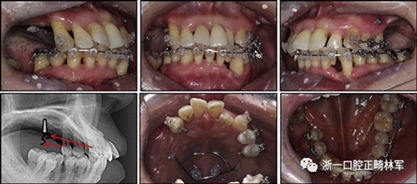

由于患者有多個缺失的后牙,因此考慮到具有垂直方向的喪失。然而,她在拔除后牙后立即去正畸科就診。她封閉了天然的左側(cè)前磨牙,并且沒有前牙的咬合磨損。因此,垂直維度被維持是確定的。在正畸治療過程中,牙種植體植入在上頜后牙區(qū)和下頜右側(cè)第一磨牙的位置(圖9)。經(jīng)過3個月的骨結(jié)合后,種植體用臨時冠修復(fù)以支持垂直維度。

圖9. 上頜牙齒推向遠中,糾正下頜左側(cè)磨牙的傾斜度,并放入種植體

在患者適應(yīng)了垂直維度和咬合后,裝置被去除(圖10)。主動治療時間為17個月。牙列立即用固定的保持器進行保持,保持器從下頜一側(cè)前磨牙到另一側(cè)前磨牙,以及從上頜一側(cè)前磨牙到另一側(cè)前磨牙的臨時牙冠上。此外,真空成型的保持器應(yīng)用于上下兩個牙弓。患者被轉(zhuǎn)診給修復(fù)??漆t(yī)生進行進一步的修復(fù)手術(shù),還轉(zhuǎn)診給牙周病專家進行維護和隨訪。在最終確認她的穩(wěn)定咬合和適應(yīng)后,進行最終修復(fù)體修復(fù)。